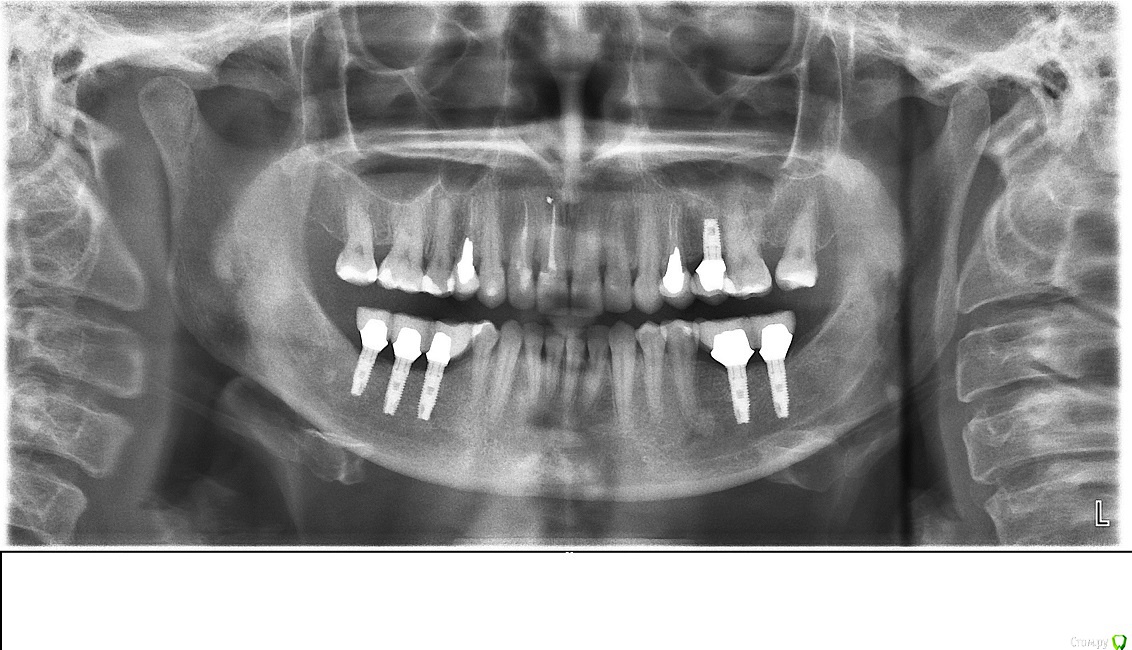

Таня-К Опубликовано 21 декабря, 2014 Поделиться Опубликовано 21 декабря, 2014 Добрый день, уважаемые врачи! Прошу Вашей консультации по имплантам. Импланты установлены в ноябре 2012 года, запротезированы в апреле 2013 (снимок 1 сделан в августе 2013). В октябре 2014 заменены коронки с целью улучшения окклюзии и эстетики, поскольку были мышечные боли и парафункции. Снимок 2 - новое протезирование.Проконсультируйте, пожалуста, произошла ли резорбция десны вокруг имплантов слева (там где три) и существует ли на данном этапе угроза для имплантов? Ссылка на комментарий